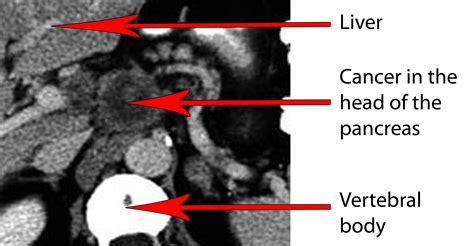

Pancreatic adenocarcinoma is a particularly aggressive form of pancreatic cancer that originates in the exocrine cells of the pancreas. Early detection and accurate diagnosis are crucial for effective treatment. One of the most important diagnostic tools for pancreatic adenocarcinoma is the Pancreatic Adenocarcinoma CT Scan. This imaging technique provides detailed images of the pancreas and surrounding tissues, helping healthcare professionals to identify tumors, assess their size and location, and plan appropriate treatment strategies.

Pancreatic adenocarcinoma is the most common type of pancreatic cancer, accounting for about 90% of all pancreatic cancer cases. It typically develops in the cells that produce enzymes to aid in digestion. The pancreas is located deep within the abdomen, making it difficult to detect tumors through physical examination alone. Symptoms often do not appear until the cancer has advanced, which is why early detection through imaging techniques like CT scans is so important.

A Pancreatic Adenocarcinoma CT Scan is a non-invasive imaging procedure that uses X-rays to create detailed cross-sectional images of the body. These scans are particularly useful for diagnosing pancreatic adenocarcinoma because they can:

• Detect tumors in the pancreas.

• Determine the size and location of the tumor.

• Assess the extent of the cancer's spread to nearby organs and lymph nodes.

After the Pancreatic Adenocarcinoma CT Scan, a radiologist will review the images to look for any signs of pancreatic adenocarcinoma. The results will be sent to the referring physician, who will discuss them with the patient. The scan results can provide valuable information, including:

• The presence and location of any tumors.

• The size and shape of the tumor.

• Whether the tumor has spread to nearby organs or lymph nodes.